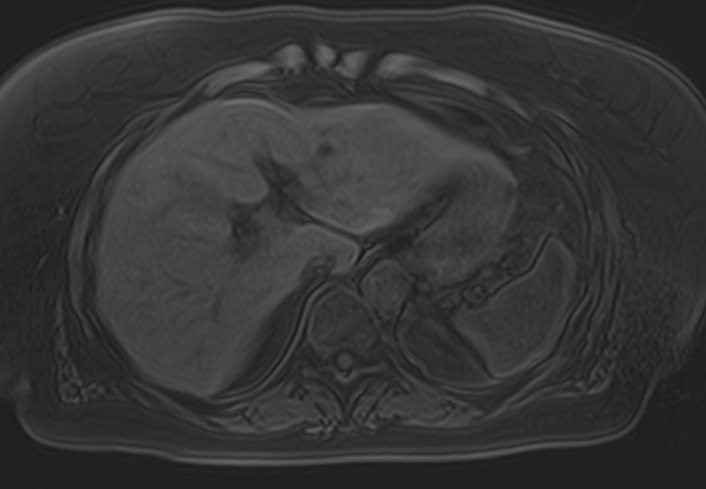

Магнитно-резонансная томография является современным наиболее информативным методом диагностики заболеваний печени. С помощью использования магнитного поля, обладающего высокой индукционной мощностью, МРТ позволяет получать послойные изображения органа и окружающих тканей и выявлять патологические изменения в печени на самых ранних стадиях развития, когда другие методы диагностики не дают результатов.

Для повышения качества визуализации патологических очагов поражения дополнительно применяется контрастное усиление. Для этого в вену вводится контрастный препарат, содержащий гадодиамид (соли металла гадолиния). Контраст позволяет оценить степень и характер васкуляризации в очагах поражения. Методика применяется для ранней диагностики как первичных опухолей печени, так и метастатического поражения, что имеет решающее значение для проведения своевременного лечения.

В клинике «Доступная медицина» исследование проводится на современном высокопольном томографе экспертного класса TOSHIBA VANTAGE TITAN 1,5 Тесла. Аппарат послойно сканирует исследуемую зону в трех плоскостях с шагом от 1 мм, при этом получая данные о структуре органа в мельчайших подробностях. Инновационные компьютерные программы реконструируют данные в трехмерные модели органа, отображающие состояние не только паренхимы печени, но и внутрипеченочных желчных протоков и сосудистой системы.